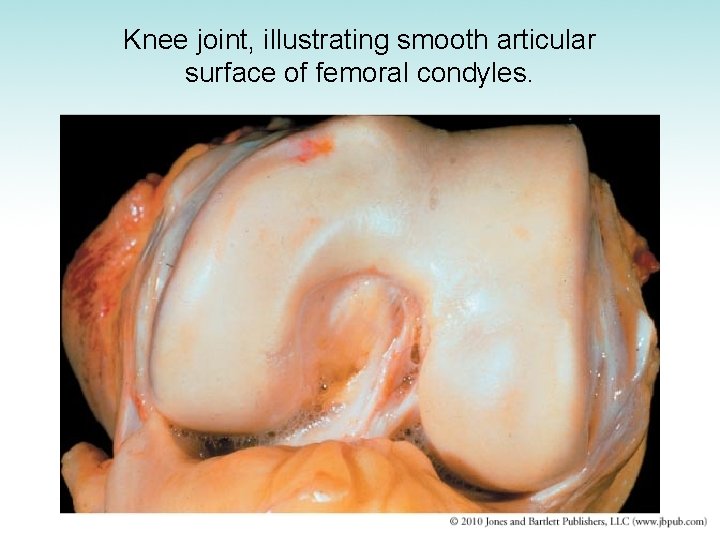

Knee joint, illustrating smooth articular surface of femoral condyles.